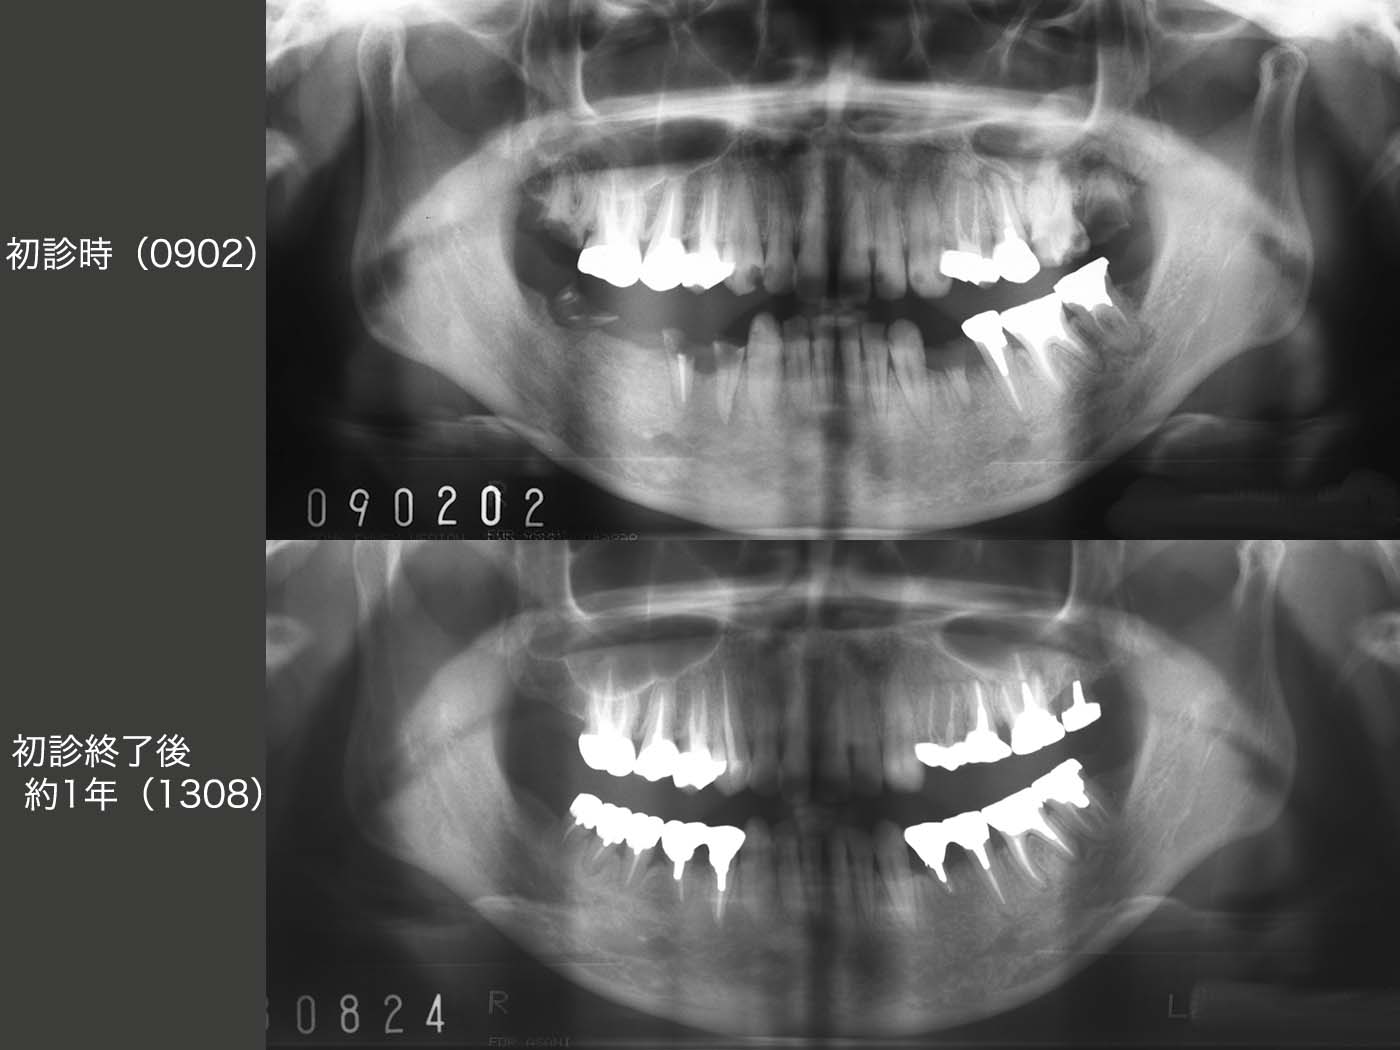

4.移植でやり繰りし、義歯を回避

2009年2月初診,26歳の女性.主訴は義歯を入れて欲しい.とにかく歯医者嫌いで恐怖心が強い.そうでなければここまで放置しないはずである.幼児期に治療を受けた嫌な思い出がトラウマになって歯医者にかかれない人は結構いると思われる.勇気を振り絞って来院したことをまずは褒め,とにかく信頼関係の構築に主眼を置き,徐々に治療を行っていった.右下の残根を抜歯し,そこに義歯を装着することは簡単だが,右下犬歯にクラスプが見えるのは審美的に耐えられないであろう.それでは,インプラントを用いるかといっても,費用が高く経済的に厳しい.

そこでまず,10年3月に左上7の残根を抜歯し,口蓋根のみを再植した.つぎに右上7を分割抜歯したところ,3根ともに歯根膜が付着しており,条件が良かった.そこで,それぞれを右下に移植した.なお右下7は,根長が短くさすがに保存できず,この症例で唯一抜歯となった歯である.抜歯後の顎堤が細かったが,3根を一直線に並べることで対応できた.

残りの治療を行い,初診から3年4ヵ月を費やし,何とか治療を終了することができた.

初診時と初診終了後約1年のパノラマX線写真の比較(妊娠したため,初診終了時のパノラマX線写真は撮らず).私自身も治療結果には満足している.しかし,問題はその後である.患者さんは最初の1回,リコールに応じたが,その後は一度もリコールに応じてくれない.結婚し,子供が2人出来,仕事も常勤でこなし,とても忙しいとのことである.たまに近所で会うと,私が“一度見せてください” 彼女が“分かりました”とは言うもののもう5年,一度も来院されていない.口の中がどうなっているかとても心配であるが,本人が来てくれない限りどうしようもない.“歯”・“口”・“人”というが,つくづく“人”との関係が一番難しいと痛感する次第である.